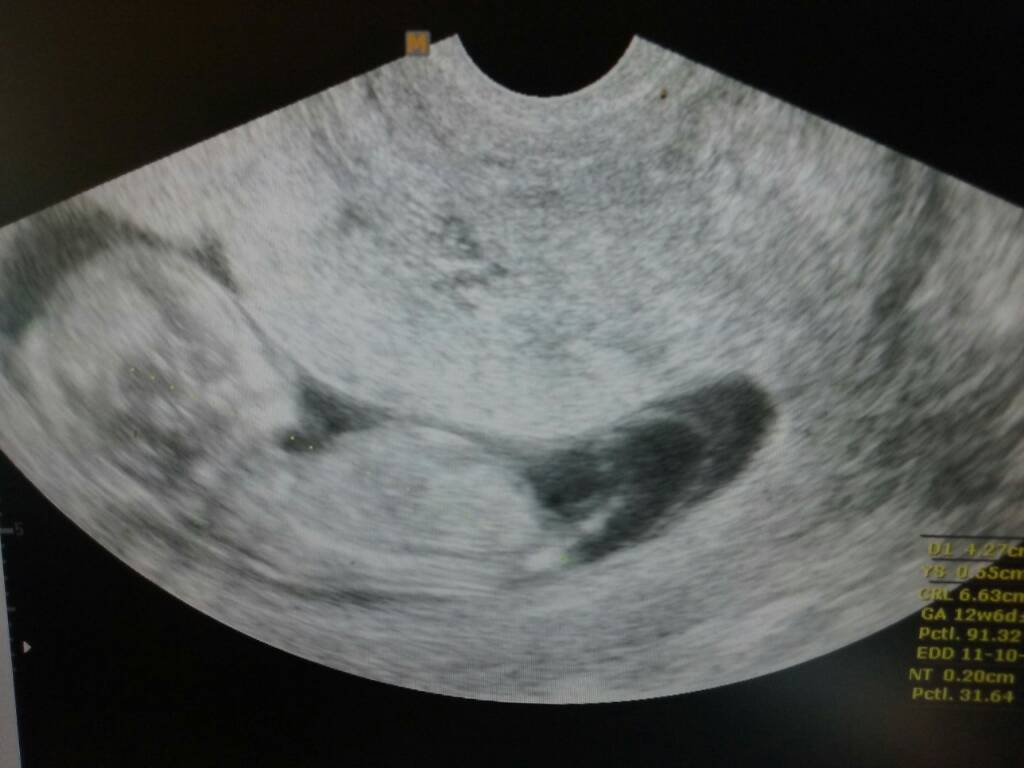

Hej ja już po usg, dzidzia ma 6,63 cm czynność serca 157/min. Rozwija się prawidlowo, żołądek i pęcherz widoczne. Dzidzia tak jest ułożona że lekarz aby ja pomierzyć musial mi robić usg dowcipnie i przez brzuch [emoji6]

Hej ja już po usg, dzidzia ma 6,63 cm czynność serca 157/min. Rozwija się prawidlowo, żołądek i pęcherz widoczne. Dzidzia tak jest ułożona że lekarz aby ja powierzyć musial mi robić usg dowcipnie i przez brzuch [emoji6]